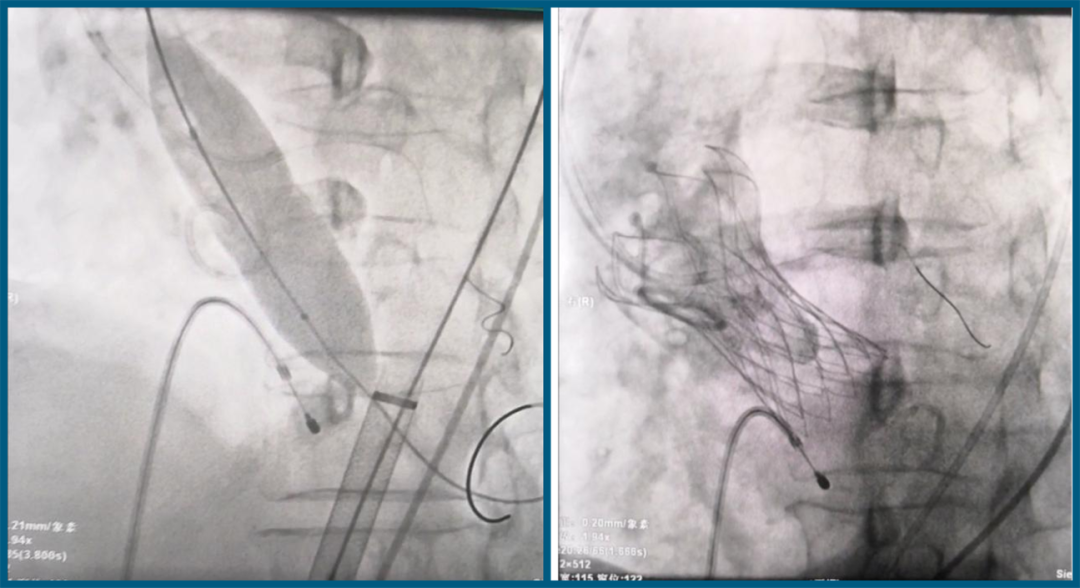

术中瓣膜释放

TAVR手术是心血管内科技术中难度最高的手术之一,也是心血管介入领域具有里程碑的技术。术中需要超声科、麻醉科等多学科的密切配合。唐秀革院长带领心血管内科团队,在麻醉科主任蓝英年的全麻辅助下,联合实时经食道心脏彩超和DSA影像学指导,顺利将人工心脏瓣膜经右股静脉植入心脏主动脉。瓣膜植入后,超声科副主任黄慧琨立即作经食道心脏彩超检查,确定更换的人工瓣膜正常工作,且功能良好。成功完成了不开胸也能换“门”的TAVR手术。